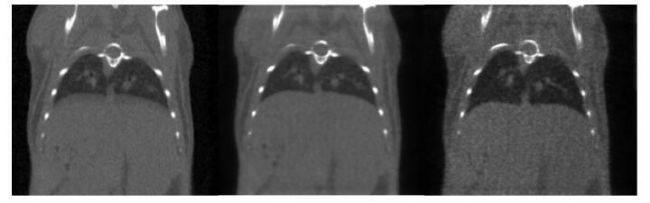

圖 5.

CT 呼吸門控圖: 超高時(shí)間分辨率(10ms) , 4min, 390mGy。 左圖: 整體整合的圖。 中圖: 呼氣結(jié)束時(shí)的圖, 右圖: 吸氣結(jié)束時(shí)的圖, 兩者顯示肺的容積相差 34%【1】 。